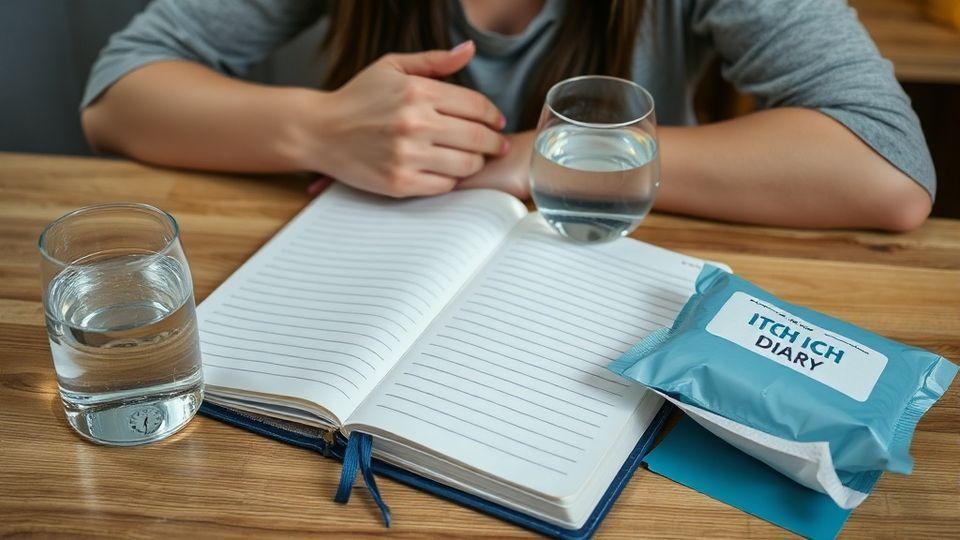

📝 실천 방법 4가지: 일지부터 생활습관까지

가려움 일지를 작성해 시간, 부위, 강도를 기록하면 의사가 훨씬 정확한 진단을 내릴 수 있습니다. 아침에 미지근한 물 한 잔은 신장과 간이 모은 독소를 씻어내는 데 큰 도움이 됩니다. 밤 11시 이전에 잠자리에 드는 것은 간의 해독 기능을 최적화하는 중요한 습관입니다. 💰